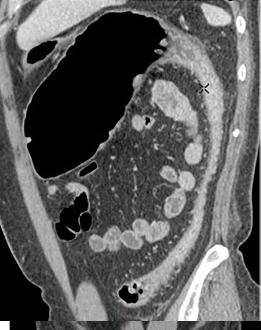

Aspect radiologique TDM

du megacolon . La colon transverse est tres dilate

en aerique . Image TDM en coupe coronal |

Meme cas

en coupe TDM sagitale . La portion innertie se

voyait longitudinal en arriere |

Toxic megacolon dans

maladie de Crohn . Image de distension du colon

transverse avec image de stenose inflamatoire et

epaissisement du colon sigmoigienne . Image

radiologique TDM en coupe coronale |

|

Meme cas en

coupe coronal a traver la colon transverse

. Maladie |